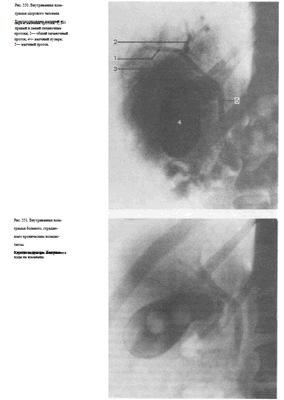

Рис. 534. Рентгенограмма сердца в левой косой проекции. Норма.

1—восходящая аорта; 2 —пра- вое предсердие; 3— правый желудочек; 4— левое предсердие; 5—левый желудочек.

Рис. 535. Рентгенограмма сердца в левой косой проекции.

Митральный порок. Увеличение левого и правого желудочков.